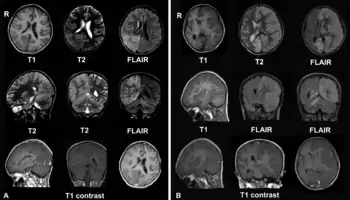

A. Декабрь 2008. У больной была головная боль и epilepsia partialis continua. Обратите внимание на очаги с фокальным отеком мозга в правой теменной и затылочной долях и правом полушарии мозжечка.

B. Апрель 2009. Та же больная, которая теперь в коме с epilepsia partialis continua. Отмечается прогрессирование энцефалита с вовлечением левого полушария мозга и значительным отеком мозга и смещением срединных структур.